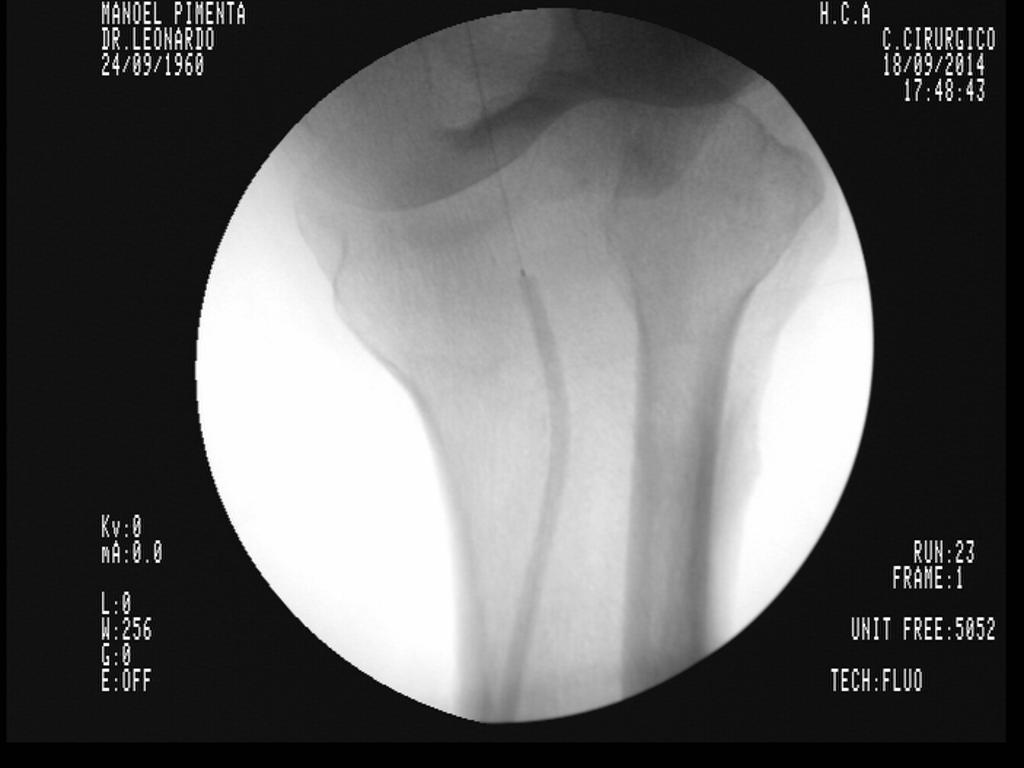

Arco Cirúrgico Radius S/R

Aplicações do Radius (alguns exemplos)

• Ortopedia

• ​Reduções de fraturas

• Implantes de próteses

• Traumatologia

O arco cirúrgico de maior confiabilidade e versatilidade do segmento, líder de mercado e com diferentes configurações para atender as necessidades especificas de cada serviço.

Características Técnicas

• Gerador 3,5 kW (anodo fixo) ou 5,0 kW (anodo giratório)

• Memória em HD de até 350.000 imagens

• Intensificadores de 9 ou 12 polegadas

• Subtração em tempo real

• Aquisição de até 30 imagens por segundo

• Dois monitores

• Porta USB

• Gravador de CD/ DVD

• DICOM